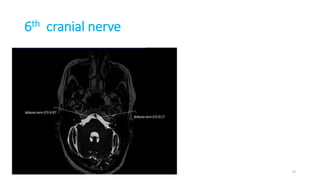

6th cranial nerve

73